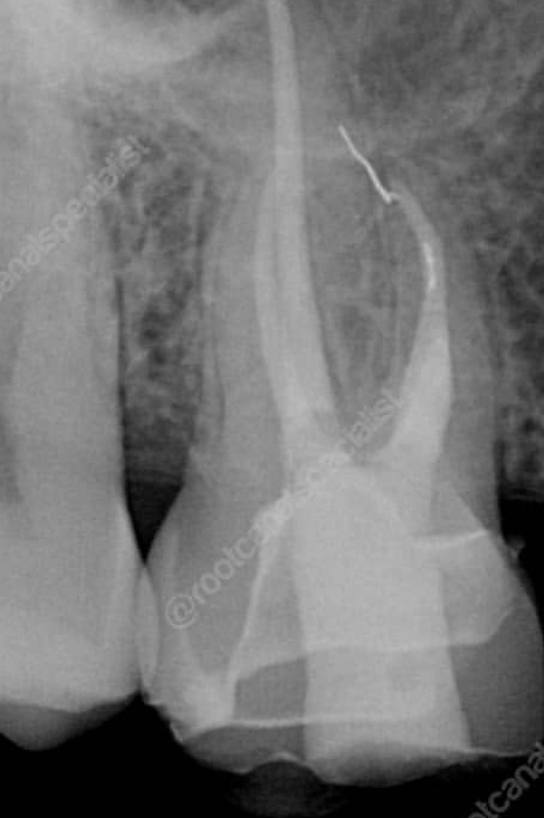

4. What type of perforation is being treated by an endodontist in this X ray?